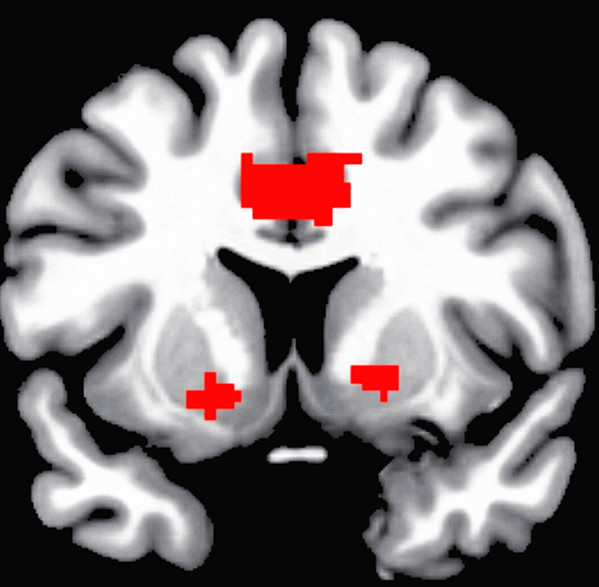

研究人員以「功能性核磁共振造影」技術,分析男性受試者在觀看色情影片時,腦部活躍的區域。特別的是,這些受試者都有明顯的「強迫性性行為」,有人曾在上班時觀看色情圖片遭開除,也有人表示觀看色情影片會促使他們召妓,而且開始接觸色情資訊的年齡普遍較低。

結果顯示,受試者在觀看色情影片時,主導情緒的「杏仁核」、影響行為動機的「腹側紋狀體」,以及與「回饋機制」及藥物渴求行為有關的「背側前扣帶迴」等部位,比起一般受試者都特別活躍。

此外,年紀愈小的強迫性性行為傾向者,腹側紋狀體愈活躍;劍橋大學博士維拉蕊佛恩解釋,腹側紋狀體與強迫性、重複性的行為有關,過去多認為可能是造成青少年衝動、危險、犯罪行為的原因之一。